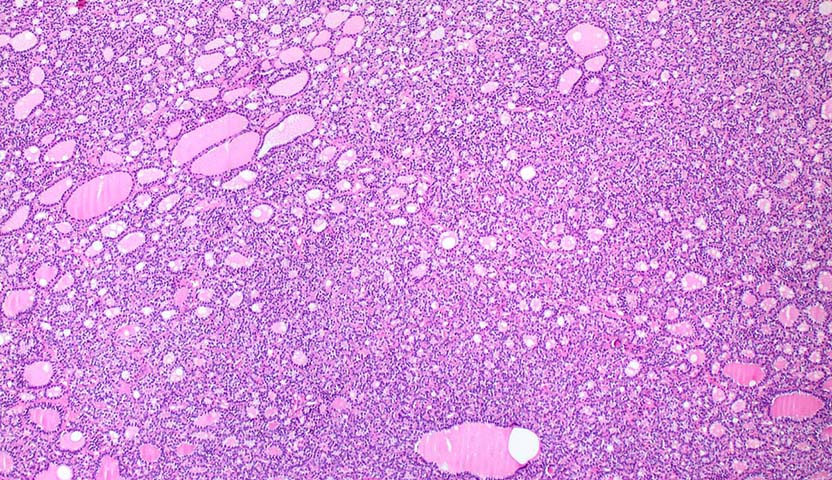

- مرحلة السرطان التي وصل لها المريض (مدى حجمه، ومكان تواجد السرطان داخل الجسم، وكيف يبدو تحت المجهر).

سرطان الغدة الدرقية الجريبي ليس شائعًا، فهو يمثل فقط 10% من أنواع سرطان الغدة الدرقية، مع ذلك وفي بعض الحالات، يصعب تشخيص هذا المرض، وفي هذه الحالة، يحتاج الأطباء إلى إجراء عملية جراحية لاستئصال الفص وتأكيد التشخيص قبل وضع خطة العلاج.

- استئصال جزء واحد أو أكثر من الغدة الدرقية: يمكن استخدام الجزء الذي تم استئصاله لتأكيد تشخيص سرطان الغدة الدرقية الجريبي.

- استئصال الغدة الدرقية كاملة: وهذا الإجراء يتم بعد تأكيد التشخيص بسرطان الغدة الدرقية الجريبي، عن طريق تحليل الفص الذي تم استئصاله.